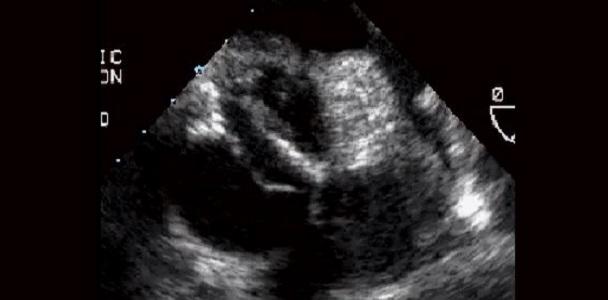

Photo Credit: (Captured from Video) ©2014 American College of Cardiology. Used with permission from the American College of Cardiology